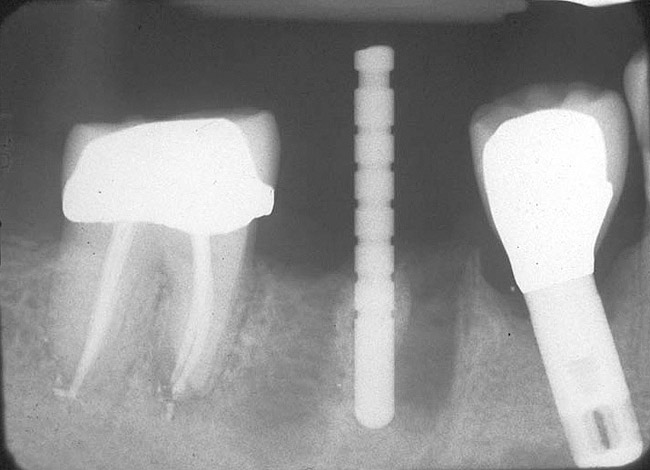

If the most crestal aspect of the interradicular bone is at least 3-mm-wide mesio-distally: A 2.2-mm-wide guide bur is drilled to the appropriate length, a guide pin is inserted, and a radiograph is taken (Figure 7). If necessary, the initial osteotomy is extended apically. A tapered osteotome is inserted into the osteotomy and moved mesio-distally and bucco-lingually to expand the osteotomy site. A 2.8-mm bur is used to prepare the osteotomy to depth, and a 2.8-mm-wide tapered osteotome is inserted in the osteotomy and once again utilized in mesio-distal and bucco-lingual directions to expand the osteotomy site. If the mesial and distal aspects of the interradicular bone are still intact at this point, a 3.5-mm bur is utilized to prepare the osteotomy to depth. A 3.5-mm-wide osteotome is inserted into the osteotomy and utilized in the manner already described. A decision is made as to whether to place a tapered implant with a 4.1-mm-wide base and a 6.5-mm-wide neck, or to use a 4.8-mm-wide bur and prepare the osteotomy to depth, in anticipation of placement of an implant with a 4.8-mm-wide parallel wall body and a 6.5-mm-wide platform. The chosen implant is inserted into the osteotomy (Figure 8), appropriate regenerative materials are placed, and the flaps are sutured. Following maturation of the regenerating hard tissues, the implant is ready for restoration (Figure 9). A radiograph taken 54 months after implant restoration demonstrates stability of the peri-implant crestal bone (Figure 10).

Figure 7  Following removal of a mandibular first molar an osteotomy was performed in the interradicular bone, a guide pin placed, and a radiograph taken.

Figure 7

Figure 8  A straight-walled implant with a 4.8-mm diameter and a 6.5-mm restorative platform diameter has been placed in the interradicular bone following tooth sectioning and removal. Primary stability has been attained.

Figure 8

Figure 9: Following manipulation of the interradicular bone, implant placement, and performance of concomitant regenerative therapy, the hard tissues are mature and the implant is ready for restoration.

Figure 9

Figure 10  A radiograph taken 54 months after implant restoration demonstrates the stability of the crestal peri-implant bone.

Figure 10